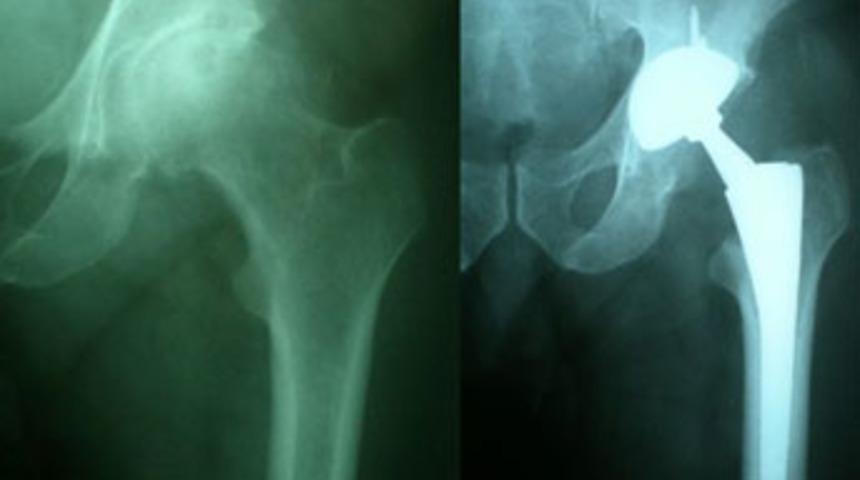

Kalça protezi skandalı

“DePuy” tarafından üretilen ve tüm dünyada satışı yapılan kalça protezinin hatalı çıkması skandala neden oldu.

Bugüne kadar ameliyatla protezi taktıran binlerce hastanın tekrar bıçak altına yatması gündemde. ALMAN Spiegel Dergisi’nin haberine göre ABD’li Johnson&Johnson şirketinin yan kuruluşu olan DePuy, kalça protezini piyasadan geri çekme kararı aldı. Sadece Almanya’da 5500 hastanın bu firmaya ait kalça protezinden taktırdığı bildirildi. Haberde “Şu ana kadar binlerce hasta tekrar bıçak altına yatarak taktırdığı kalça protezini çıkarttırmak zorunda kaldı. Uzmanlar, önümüzdeki dönem bu protezi taktıran her hastanın tekrar ameliyat olmak zorunda olduğunu düşünüyor. Olay, Almanya tıp tarihinin en pahalı skandalı olma yolunda. Yapılması gereken ameliyatlar nedeniyle milyonlarca Euro’luk masrafın meydana gelmesi bekleniyor” yorumu yapıldı. Dünya genelinde satış yapan Johnson&Johnson’ın zararı düşürmek için sağlık sigortaları ile görüşmelerini sürdürdüğe dikkat çekilirken “Milyarlarca Euro’luk bir piyasa payı bulunuyor. Şirketler yeni ürünlerini pazarlamanın peşinde.”

ÜRETİCİ firma tarafından hatalı olduğu gerekçesiyle geri alımı yapılacağı duyurulan kalça protezleri Türkiye’de de kullanılıyor. Sağlık Bakanlığı yetkilileri, konuyla ilgili olarak Hürriyet’e şu bilgiyi verdi: “Protezlerde tasarım hatasından kaynaklı eğilme, kırılma, erken değiştirmeyi gerektiren deformasyonlar olmuş. Bu nedenle firma Temmuz 2010’dan itibaren ürünü geri çağırmış. Bu protez Türkiye’de de satılmış ve kullanılmış. Firma konuyla ilgili acil güvenlik uyarısını doktorlara yapmış. Bakanlık olarak saha düzeltici faaliyet raporu düzenledik. Ürün temmuz ayından itibaren kullanımdan kaldırıldı. Kullanılan kişilerden ürünle ilgili bugüne kadar hiçbir şikayet gelmedi. Ürünün her serisinde sorun olmayabiliyor.”